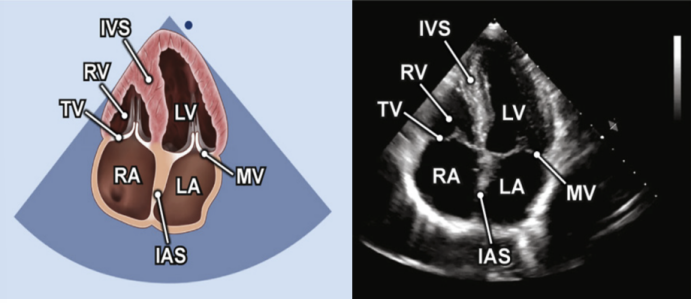

其次,观察心腔的大小。此处根据重症超声评估血流动力学的思维,先从右心评估开始。常规首选心尖四腔心切面(A4C)进行相关测量,在该切面可以测量右心室的上下径和左右径。该方法测量的三尖瓣瓣径通常小于2.8 cm,超过3.9 cm即为重度扩张。中间段直径参考值小于3.5 cm,超过4.2 cm为重度扩张。上下径小于7.9 cm,超过9.2 cm为重度扩张。操作示意图见图2。

图片

图2. 心尖四腔心切面A4C下测量右心室上下径(线段3)和瓣环径(线段1)和中间段内径(线段2)的示意图

右心房一般通过心尖四腔心切面来观察形态学大小图7,其左右内径的参考值为2.5~4.5 cm,上下内径的参考值一般小于5.2 cm。

图7. 右心房(RA)在A4C下(蓝色线段左右径,绿色线段上下径)内径测量示意图